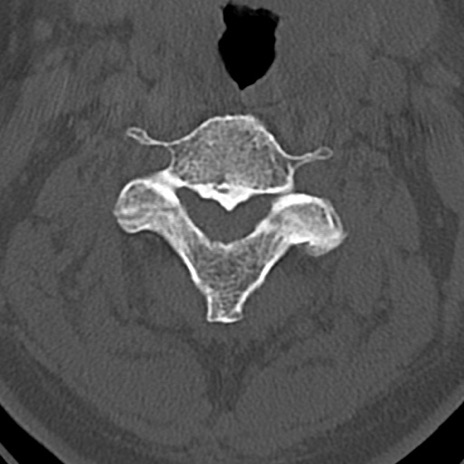

頚椎CT

横断像